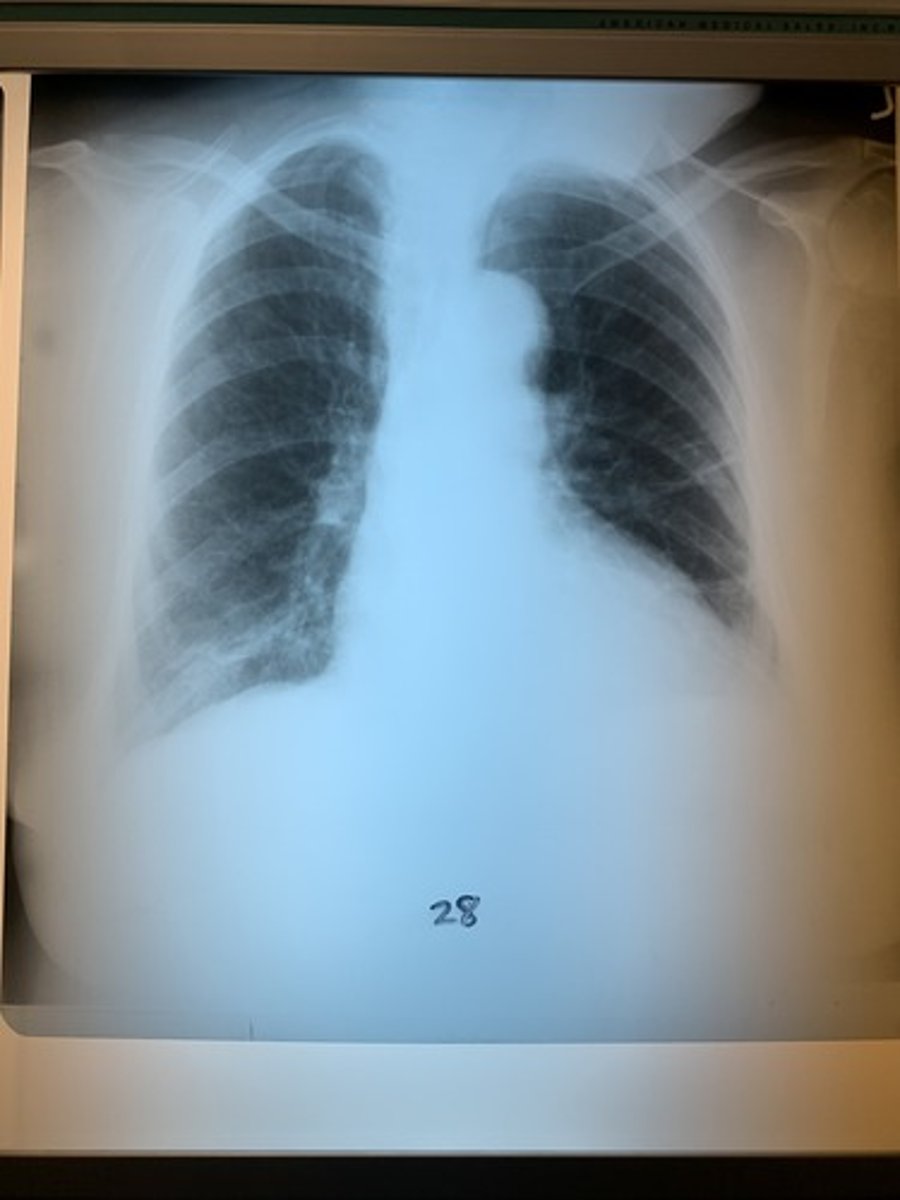

Regarding radiograph 28, is it penetrated?

Not penetrated